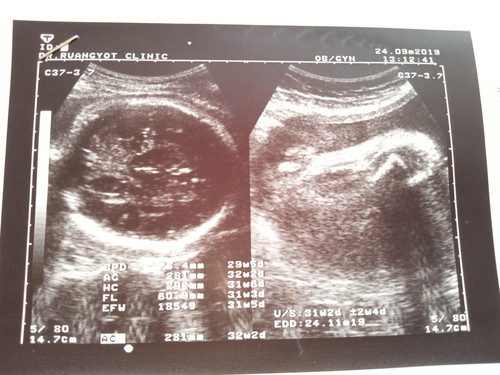

31+5วีคท้องลูกสาว

แม่ๆค่ะจะดูน้ำหนักลูกดูตรงไหนค่ะพอดีดูไม่เป็นค่ะแล้วน้ำหนักลูกอยู่ในเกณฑ์หรือป่าวค่ะ ขอบคุณสำหรับคำตอบค่ะ

น้องหนัก1854g. ค่ะ

1854กรัมค่ะ